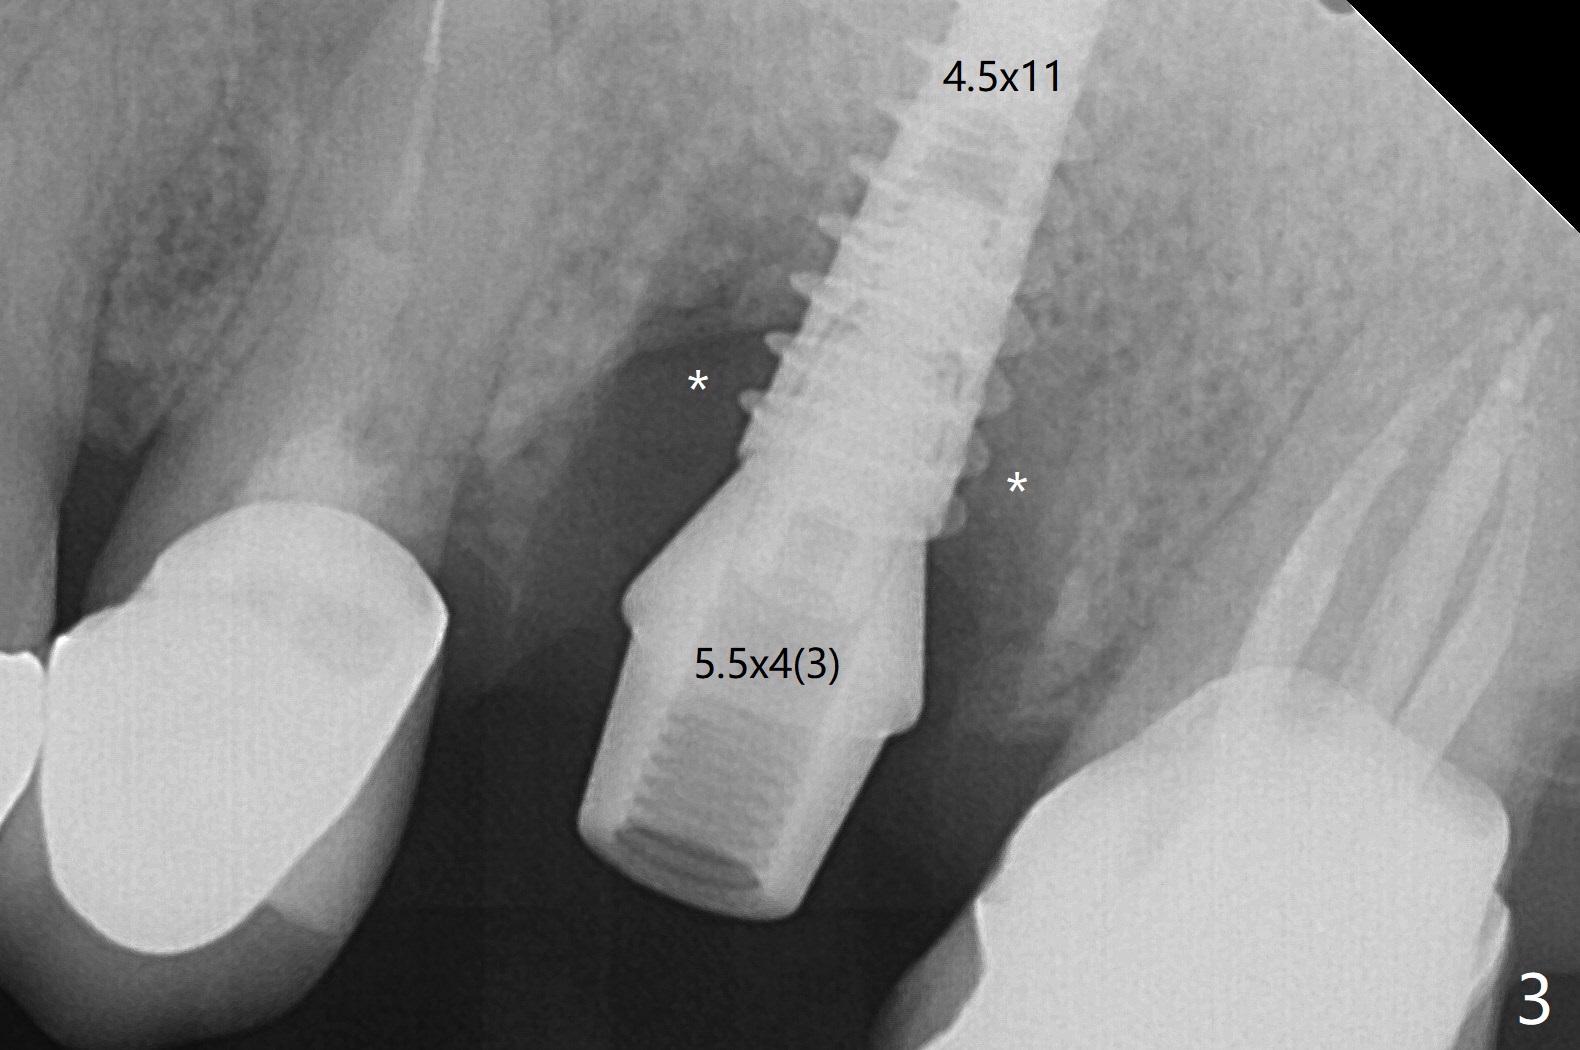

左上6腭侧退缩牙龈(图一:箭头)深部没有骨壁(图二:*),4.5x11毫米植体周围缺损(图三:*)由粘性骨粉(皮质骨,图四:*)填入,即刻临时牙冠(图五:P)覆盖腭侧缺损(空箭头)和PRF膜。临时牙冠颊腭侧做的很宽(图六),目的是关闭腭侧缺损,术后四周在不影响骨粉覆盖情况下,牙冠腭侧适当向颊侧缩小(图七:箭头),但是不应该缩短龈下边缘。术后四个月骨粉形态接近原位骨(图八),但是腭侧软硬组织仍有缺损,炎症。